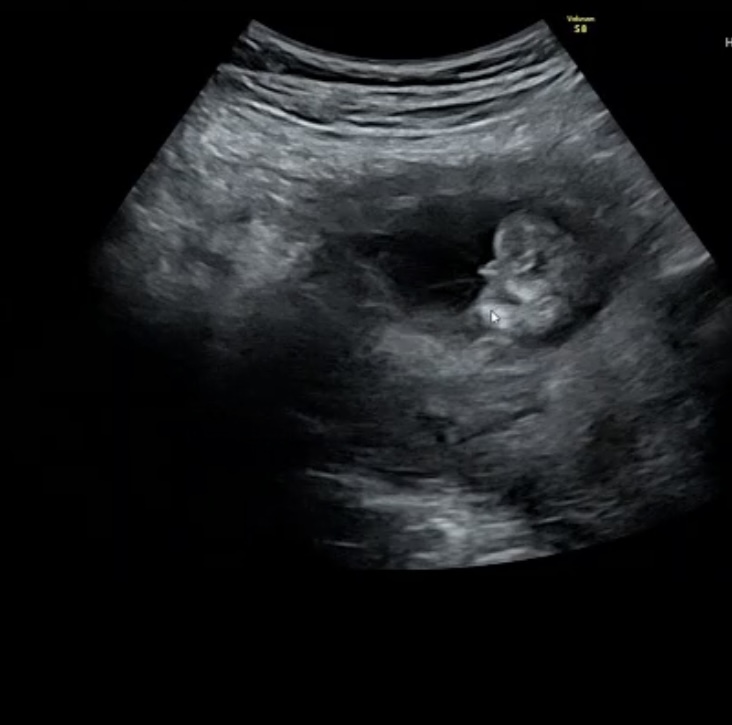

15週1日で受診した時のお話です

担当の先生からはまだハッキリしないけど男の子ぽいかなーと言われました。

エコー写真はおしりを下からみた角度になります。わたしは15週でこれくらいはっきり見えてたら確実なのかなと思いました!

お尻を下から見た角度のエコー写真だということなのですが、はっきりとお股のあたりが写っている様子には見えず、男の子のシンボルとして、見て良いのかどうか疑問に思いました。

性別を確認するのであれば、もう少しエコーで様子を見てみたいなと思いました。